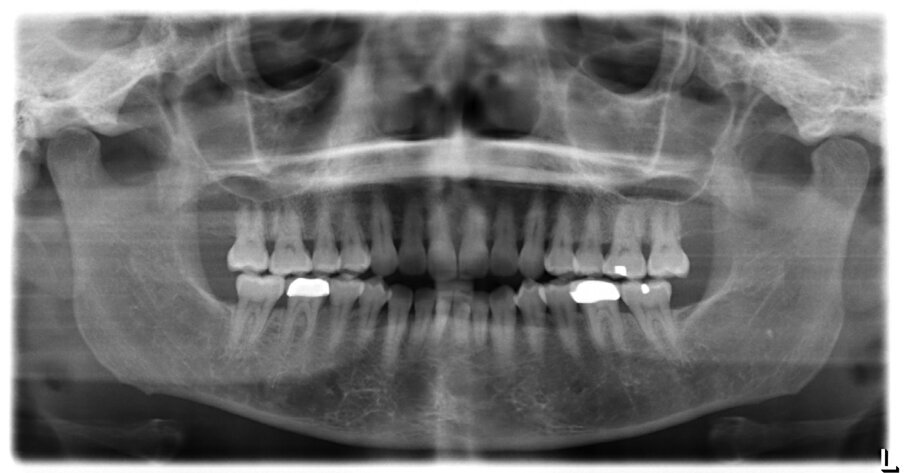

A 56-year-old female patient presented with a Class III malocclusion, anterior crowding and a 2-3 mm anterior open bite. Clinical photographs showed an ideal incisor display upon smiling. The panoramic film was unremarkable, and the lateral cephalometric film revealed a negative 1 mm overjet. (Figs. 1 to 10)

The treatment plan for this patient involved upper molar intrusion without the use of TADS in order to achieve counterclockwise rotation of the mandible and closure of the anterior open bite. Class III inter-arch elastics were prescribed to establish Class I molar and canine relationships and achieve proper overjet.

Lower arch expansion and interproximal reduction of 0.5 mm were prescribed on all of the lower incisors from mesial of canine to mesial of canine before the 19th aligner. (Fig. 13) IPR would allow retraction to assist the Class III elastic correction of the negative overjet. Additionally, since counterclockwise autorotation of the mandible would project the lower incisors anteriorly, retraction would also assist in mitigating this effect.